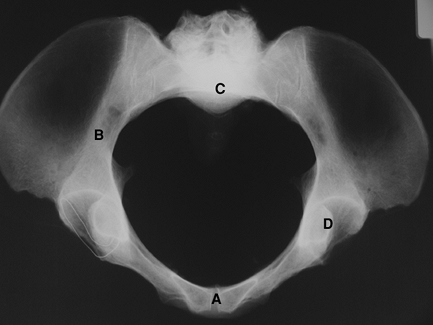

Figure 2-4 The inlet view of the pelvis. A, pubic symphysis; B, ilium; C, sacral promontory; D, acetabulum.

addition to the AP pelvis for evaluation of the bony pelvis. The inlet

view (Fig. 2-4) projects the rings of the pelvis and allows for evaluation of rotational alignment of the pelvis. The outlet view (Fig. 2-5)

projects parallel to the pelvic rim and perpendicular to the sacrum and

allows for evaluation of vertical translation or malalignment.